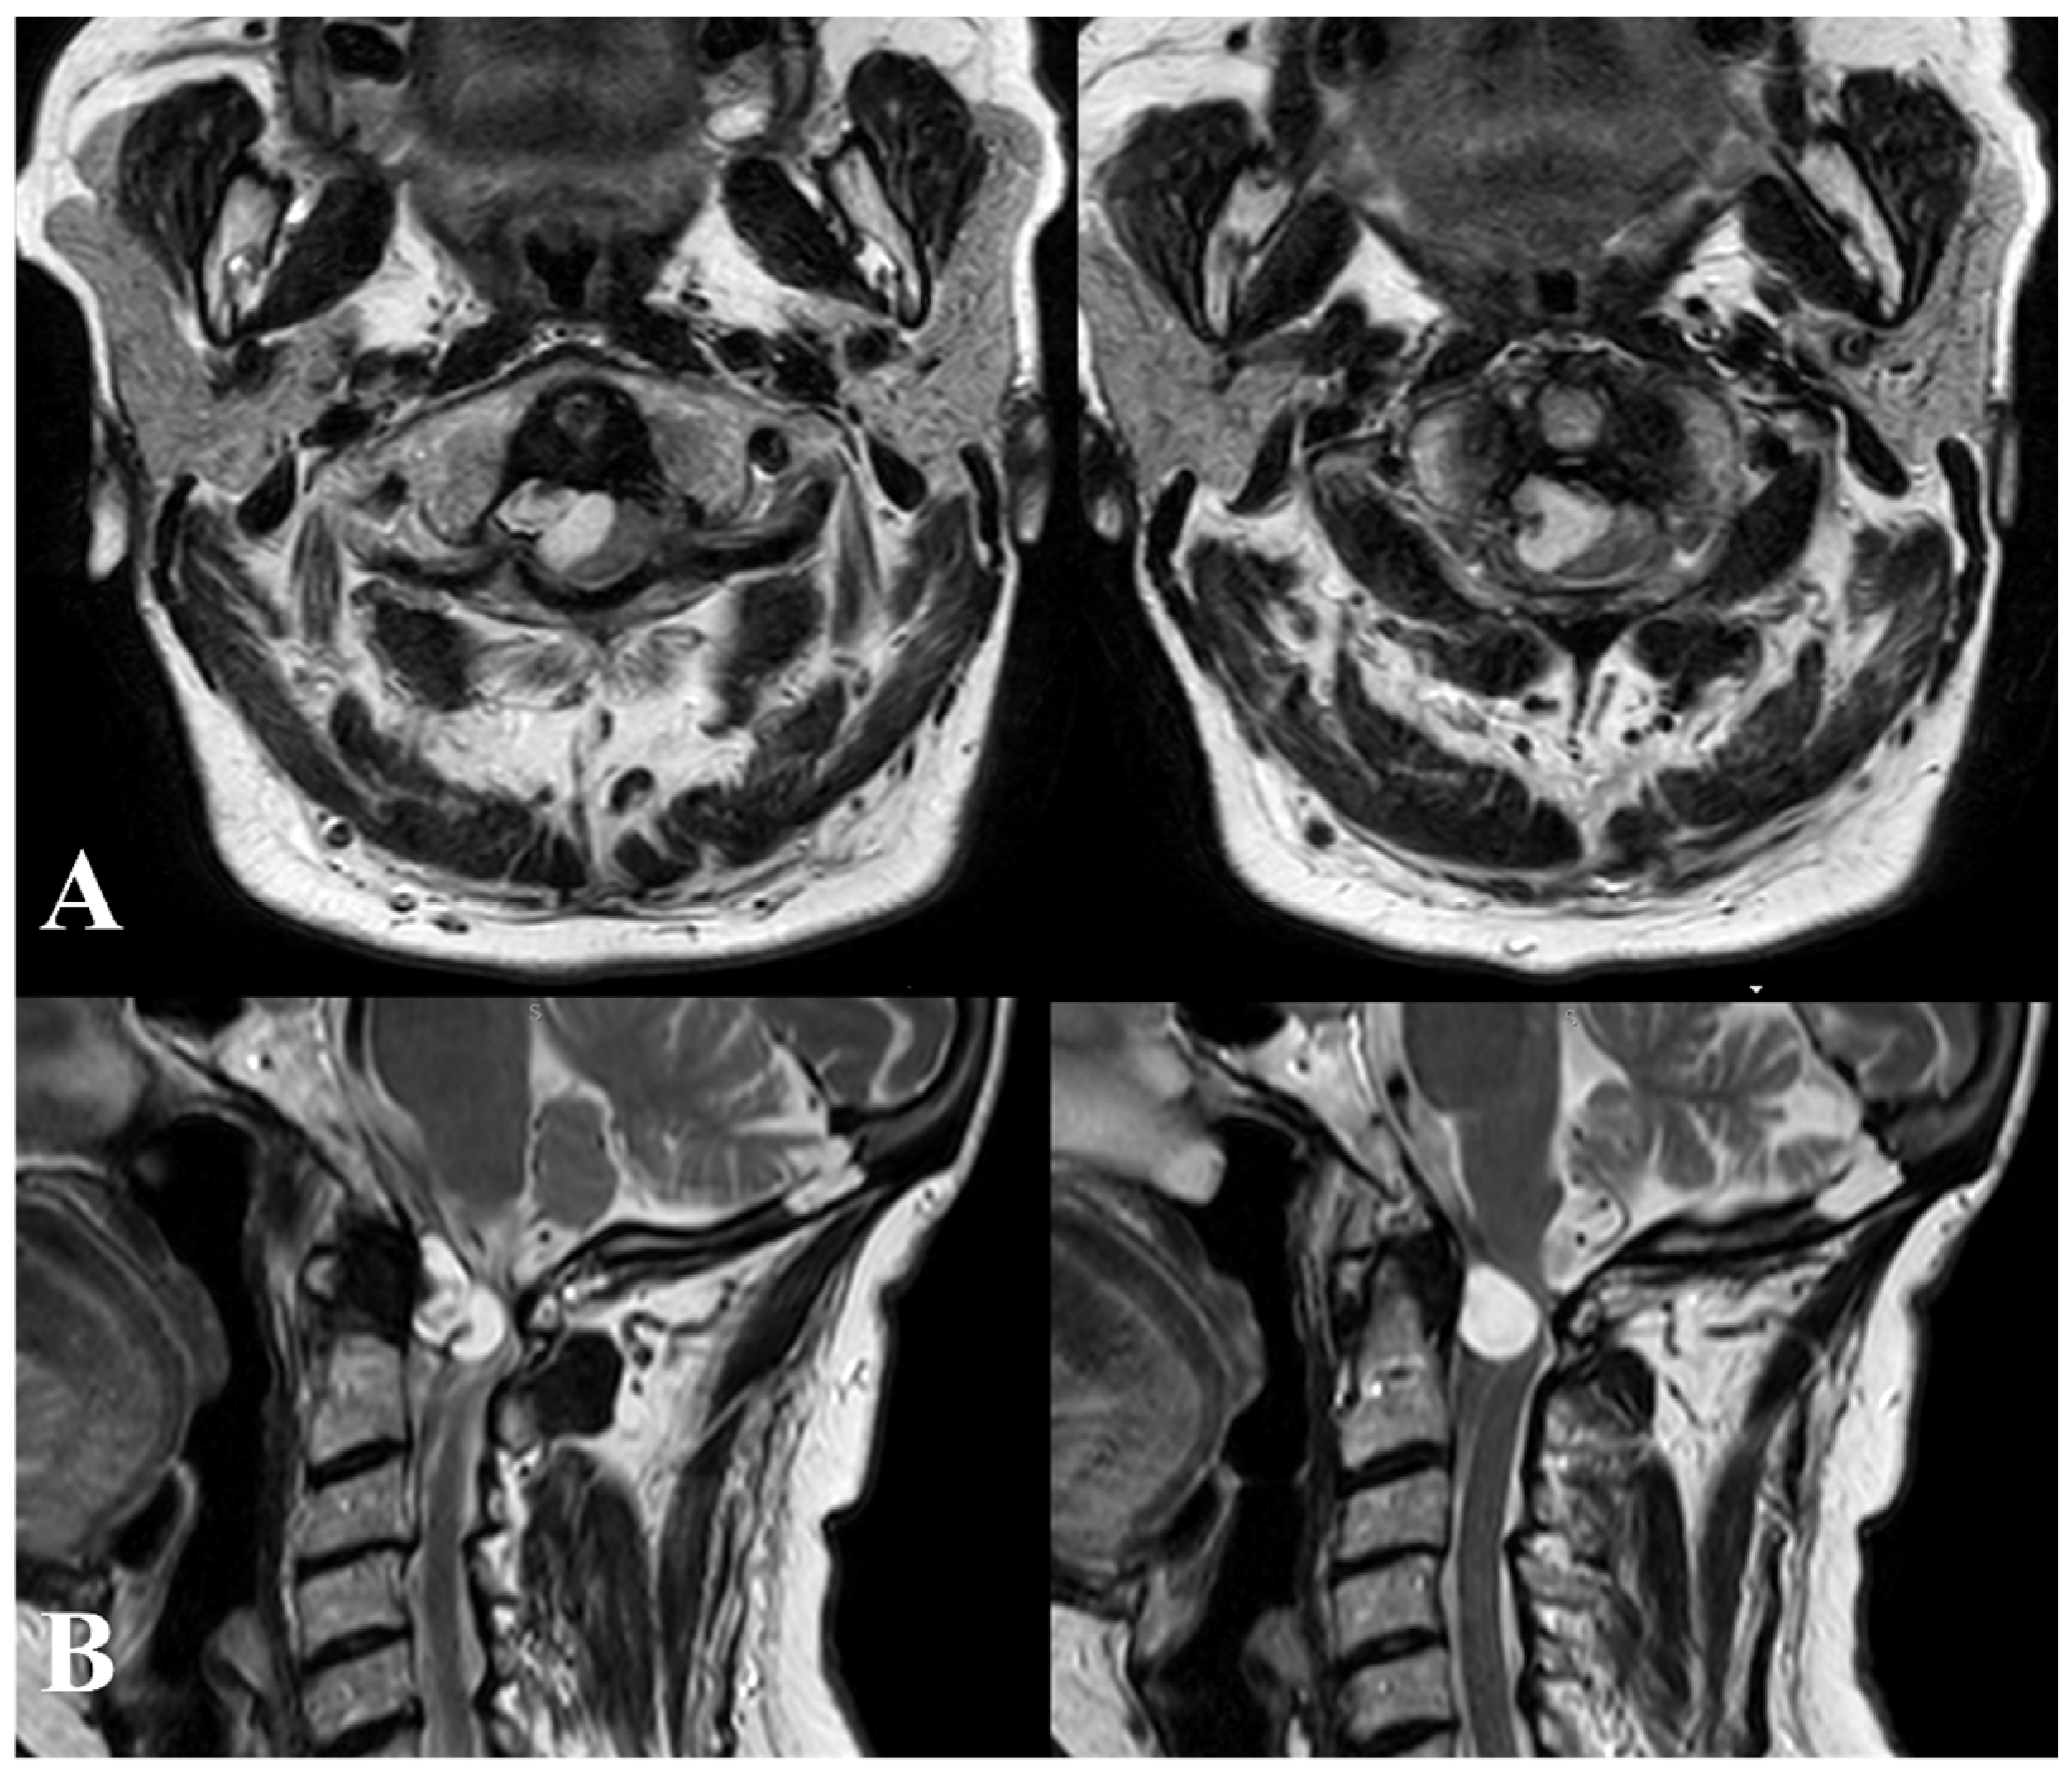

A 56-year-old woman was admitted to our institution due to a sudden onset of right hemiparesis following three days of neck pain. Upon examination, she exhibited hemi-hyposthenia (BMRC 3/5), inability to stand or walk, heightened deep tendon reflexes bilaterally (particularly on the right side), and bladder dysfunction. Additionally, she displayed nuchal rigidity and positive Kernig and Brudzinski signs. Initial hematological and coagulation tests yielded unremarkable results, and the patient had no history of vertebral trauma. Considering the abrupt symptom onset, suspicions arose regarding either a malignancy or hemorrhage from a vascular malformation. Given the concurrent presence of meningeal signs, emergency computed tomographic (CT) scanning from the brain down to the craniovertebral junction (CVJ) was conducted. The CT scan revealed an iso-hyperdense lesion at the CVJ. Subsequent T1- and T2-weighted magnetic resonance imaging (MRI) identified a large anterior, right lateral tumor measuring approximately 1.3 × 1.6 cm at the C1–C2 level. The tumor appeared hyperintense in T2WI and hypointense in T1WI, exhibiting ring enhancement after gadolinium administration (Figure 2 and Figure 3).

Figure 2.

T2-weighted magnetic resonance imaging (MRI) axial (A) and sagittal (B) images revealing a large anterior, right lateral tumor measuring approximately 1.3 × 1.6 cm at the C1–C2 level. The tumor displays hyperintensity in T2-weighted imaging (T2WI).